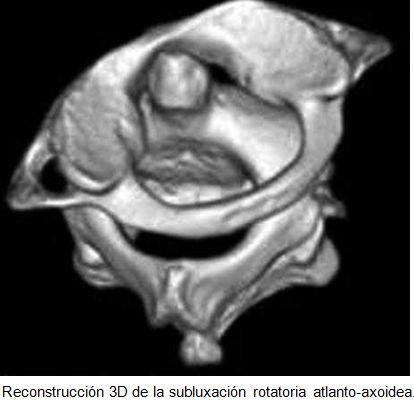

La tortícolis tiene diferentes cualidades dinámicas, dependiendo de si es no paroxística (no dinámico, por ejemplo, muscular congénita y subluxación rotatoria atlantoaxial (C1-C2) o paroxística(dinámico, por ejemplo, paroxístico benigno y espasmódica).

Varias de las patologías  mencionadas: faringitis, procesos inflamatorios de vía aérea,  puede dar lugar a la laxitud ligamentosa a nivel del atlas, permitiendo deformidad rotatoria y que resulta en tortícolis. La subluxación rotatoria atlantoaxial, es predominantemente una lesión de la infancia, aunque en ocasiones se observa en adultos.

En contraste con tortícolis muscular congénita, en subluxación rotatoria atlanto-occipital, la cabeza se inclina en sentido opuesto del músculo esternocleidomastoideo afectado, con el esternocleidomastoideo acortado, en el lado de la barbilla.

Hay un espasmo muscular en el lado del esternocleidomastoideo “largo”, lo que refleja un intento para corregir la deformidad.

Estas dos entidades se pueden separar fácilmente: en pacientes con tortícolis muscular congénita, el ECM del lado contralateral de la rotación de la cabeza se endurece, acorta y hace que la cabeza se incline. En pacientes con subluxación atlantoaxial, el músculo ECM muestra un espasmo  del lado ipsilateral a la barbilla, la que hace girar, lo que sugiere un intento de reducir la deformidad y aliviar el tejido infectado.

En la mayoría de los casos, las anomalías se resuelven en días o semanas con terapia sintomática sola, aunque de vez en cuando la deformidad persiste, lo que resulta en la fijación rotativa.

El manejo  de la subluxación rotatoria atlantoaxoideas, va desde medidas conservadoras, a la intervención quirúrgica.

El tratamiento de la tortícolis secundarias a la subluxación atlantoaxoidea,  depende de la gravedad y la duración de la subluxación.

En los casos agudos (menos de 1 semana de duración) y las menos graves, un collar cervical blando, reposo y analgésicos puede ser adecuado. Para los casos más graves, se indica tracción cervical La cirugía puede ser necesaria si tracción no tiene éxito en la reducción de la subluxación.